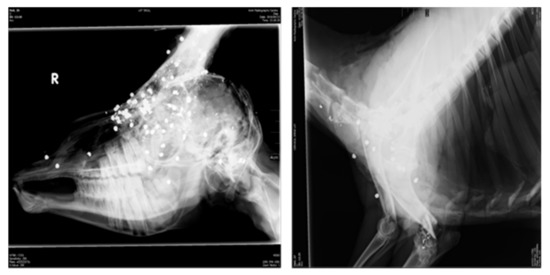

- Enforcement: Law enforcement would entail environmental pollution control, hunting and slaughter/processing control and the banning of generally used products with high concentration of toxic metals (e.g., fuel, paint) but, specifically, lead bullets and pellets used for hunting. This will ensure that secondary contamination of meat animals by these products is minimised [99,100].